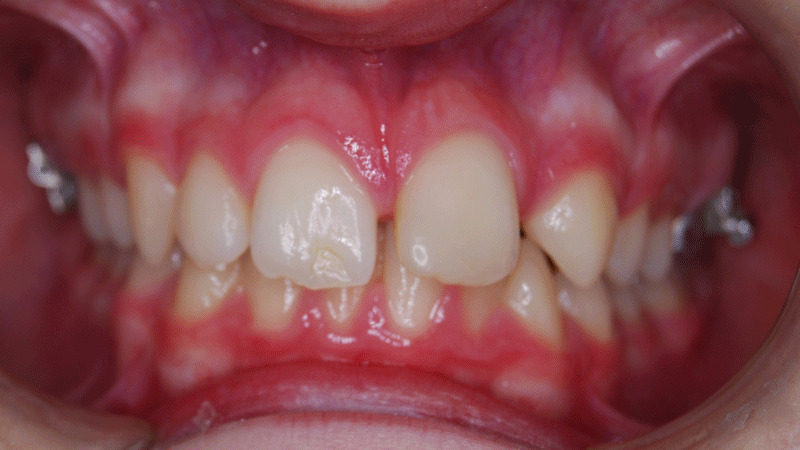

Overbite before and after

Deep bite before and after side view